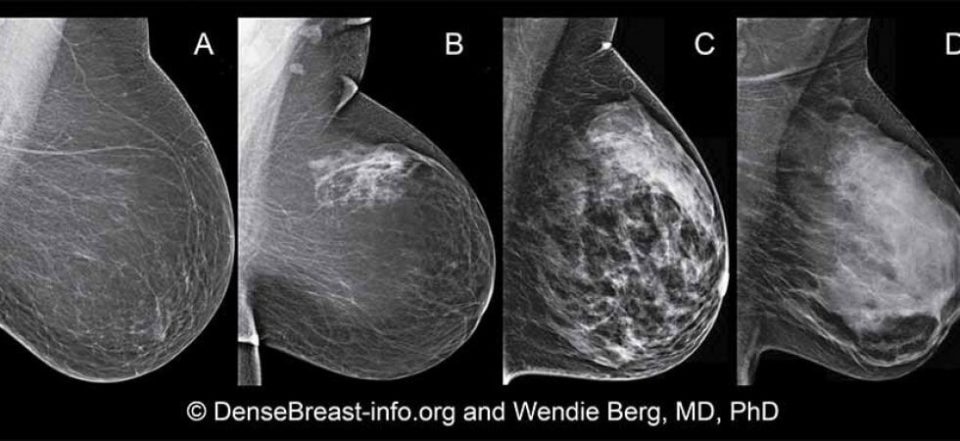

Nei prossimi LEA con buona probabilità, stando a diverse voci che si rincorrono ormai da mesi, non ci sarà l’estensione per lo screening mammografico dai 45 ai 74 anni, come richiesto invece dalle linee guida europee. Non è passato neanche l’emendamento per investire 6 milioni di euro extra LEA sulla estensione dello screening mammografico. Il dato più preoccupante è l’esclusione delle donne giovani, visto che, i numeri delle diagnosi in età giovanile sono in aumento. Il Report sui numeri del cancro in Italia (dal ministero della Salute) conferma che il tumore della mammella è la neoplasia più frequente nelle donne. Secondo i dati del report sono 925.000 le donne che vivono in Italia dopo una diagnosi di tumore della mammella. Per l’anno 2024 sono stati diagnosticati 53.686 nuovi casi (uomini=621; donne=53.065). In Italia, l’11% dei nuovi casi di tumore al seno viene appunto diagnosticato in donne sotto i 45 anni, e il trend sarebbe in aumento. L’allarme non è solo per i 6 milioni di euro negati allo screening, ma per un modello di salute pubblica “fermo agli anni ’90, quando è iniziato” che di fatto “non investe in innovazione, non ottimizza” e arriva a negare nei fatti la prevenzione, facendo di una malattia che colpisce le donne lungo tutto l’arco della propria vita anche una vera epidemia sociale. A commentare con preoccupazione questa promessa mancata dei LEA è la professoressa Adriana Bonifacino, medica oncologa, senologa e presidente della Fondazione IncontraDonna. “Non abbiamo nei LEA la fascia 45-74, e abbiamo solo la 50-69 e regioni che ciascuna diversamente investono sulla fascia più giovane o più anziana, secondo risorse; ma soprattutto abbiamo 20 regioni diverse e non un Paese unico e questo alimenta discriminazioni”. Non solo un problema di soldi quindi, ma un modello che non gira. Dalle piccole alle grandi cose. Tanto per cominciare la mancanza di una messa in rete delle cartelle screening di una singola donna. “Se faccio screening in una Asl e cambio quartiere, cambio città o regione di me non c’è nulla riguardo lo storico dello screening mammografico. Ed è la comunità scientifica che ci dice che il confronto delle immagini radiologiche è di fondamentale importanza: può far scoprire un tumore, o risparmiare una biopsia inutile, ovvero rassicurare una donna per quale si aveva un sospetto”, spiega la professoressa. È un po’ come costruire sulla sabbia un percorso che non lascia traccia. Altro tema quello dei mammografi. “Il 60-65%- dice Bonifacino- ha già una predisposizione alla tomosintesi (mammografia tridimensionale che consente di studiare il seno a strati), basta una rimodulazione con un investimento economico di portata sostenibile, soprattutto se vista in una ottica di successivo risparmio. Se la si applica allo screening di primo livello si può risparmiare nei richiami al secondo livello. Un risparmio non solo sanitario ed economico, ma anche sociale (la donna che lavora non deve prendere un altro giorno), ma anche risparmio di ansia e tempo”. Le donne sono cambiate, commenta la specialista, e il sistema sanitario non se ne è accorto. Dalla diffusione delle protesi additive, al seno denso, alla familiarità ed ereditarietà di mutazioni genetiche. Ma non solo. “Le donne lavorano, sono proiettate nel futuro in modo del tutto diverso negli ultimi 30-40 anni; il tumore nelle giovani (che rimandano la prima gravidanza per ragioni di lavoro o di welfare) è devastante, c’è anche tutta la questione dell’oncofertilità da considerare; e anche il tumore nella donna anziana è difficile da sostenere se avanzato e non precocemente intercettato, per la ricaduta familiare e sociale nella sua gestione. Solo pochi giorni fa- racconta- abbiamo operato una donna di 100 anni; ha voluto essere operata per il piccolo tumore che aveva sentito da sola nel seno perchè non vuole tornare a controlli e vuole vivere il tempo che le è rimasto senza il tumore nella mammella”. Un tempo sarebbe stato impensabile. “Dobbiamo puntare ai LEA 45-74, il Ministro si è sempre detto d’accordo, ma non si riesce. E dobbiamo- rincara Bonifacino- dare comunque indicazioni, raccomandazioni di prevenzione, al di là dello screening finanziato, alle donne prima dei 45 anni e alle anziane”. Al momento non c’è nulla, solo tante e diverse voci. che disorientano le donne nella gesstione dei propri controlli. “Se non investiamo non saremo un Paese unico e si rafforzeranno le discriminazioni”. Addirittura, sottolinea la presidente della Fondazione IncontraDonna, oggi c’è chi nega il valore dell’autopalpazione come mezzo di conoscenza del proprio corpo: “Solo nell’ultimo mese grazie all’autoosservazione tre donne si sono accorte di un cambiamento e abbiamo riscontrato il morbo di Paget”, continua per dare un esempio, una forma di cancro che si riconosce dall’osservare cambiamenti del capezzolo”. “L’incidenza del tumore seno è la più frequente dai 35 anni fino alla fine della vita per le donne”, ricorda ancora Bonifacino, mentre per gli uomini ci sono tumori diversi in base alle fasce d’età, “questo vorrà dire qualcosa?”, si domanda. Non c’è tempo per rimandare ancora: “il ‘successivamente’ della politica non si può più sentire, dobbiamo dare subito nuove indicazioni alle donne e sostenerle nei loro percorsi”. Le donne sono cambiate e il sistema sanitario pubblico no: raggiungerle, ribadisce Bonifacino, è una priorità di prevenzione, un investimento e non un costo. E’ così che dovrebbe andare.